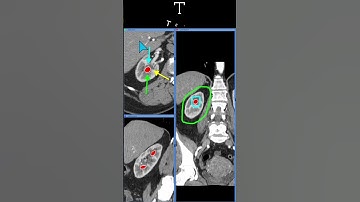

Creating label/landmark/point/fiducial marker on DICOM volume data